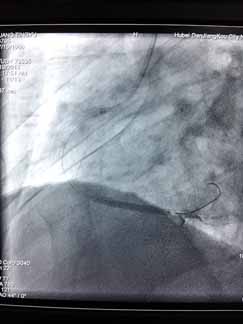

近日,烈日炎炎,急性心肌梗死高发,周六周日两天“120”急救车连续接诊两位急性心梗患者,到达我院后,心血管内科立即开通心梗绿色通道,最短时间内对两例病人实施急诊PCI,配合药物、抽吸导管及冠脉支架治疗,手术进行的非常顺利。门球时间均在60分钟内,堵塞血管立即开通,置入心脏支架,病人获得了最大收益,避免了急性心梗的高死亡率及不良后遗症。